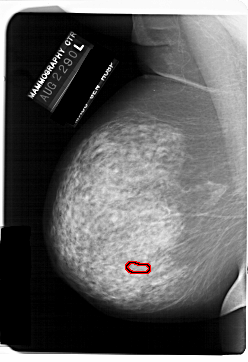

A_1146_1.LEFT_MLO

LEFT_MLO LINES 6871 PIXELS_PER_LINE 4711 BITS_PER_PIXEL 12 RESOLUTION 43.5 OVERLAY

FILE: A_1146_1.LEFT_MLO.OVERLAY

TOTAL_ABNORMALITIES 1

ABNORMALITY 1

LESION_TYPE CALCIFICATION TYPE PLEOMORPHIC DISTRIBUTION LINEAR

ASSESSMENT 4

SUBTLETY 2

PATHOLOGY MALIGNANT

TOTAL_OUTLINES 1

BOUNDARY